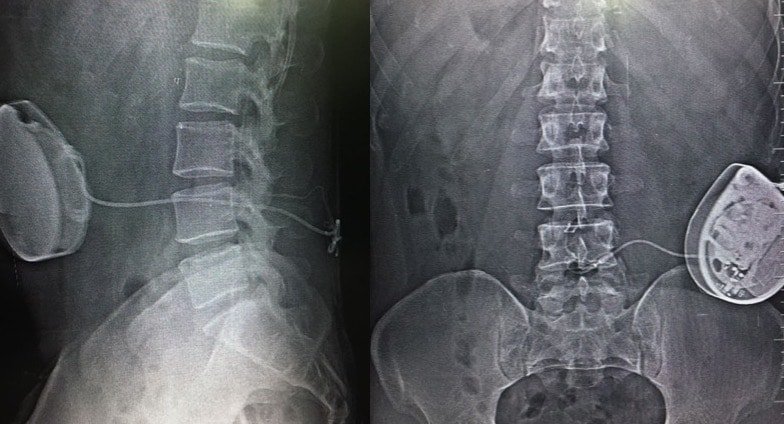

Spinal Cord Stimulator

A spinal Cord Stimulator is a special battery-powered device that is fitted over the spinal cord for the treatment of spinal pain which is not relieved by other methods.

Indications For SCS

- Failed back syndrome

- Post laminectomy pain

- Multiple failed operations

- Epidural fibrosis

- Complex regional pain syndrome